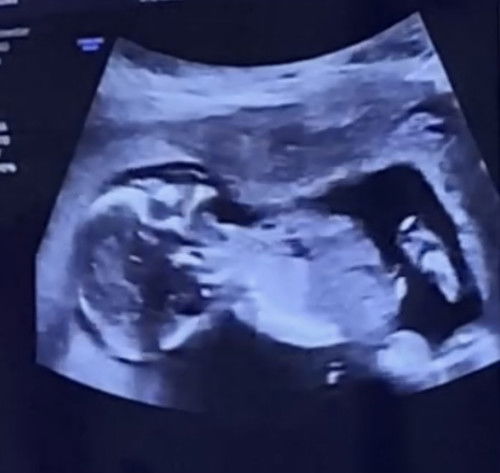

Hello mga mi ask lang po sino po nagka uti po dito? maliban po ba sa pag pa check up, inum ng antibiotic ano po ginagawa nyo po sa bahay para ma tanggal o wala UTI nyo po? bukod sa pag inum din po ng maraming tubig nakaka ubos po kc ako ng 3-4Liters. pls respect & no bashing needed. Salamat po sa mga sasagot at mag share ng opinyon.😇 #pregnancy #askmommies #Needadvice #AskingAsAMom #2ndtrimester #uti #UTIinPregnant #UTIin2ndTri #pregnancy